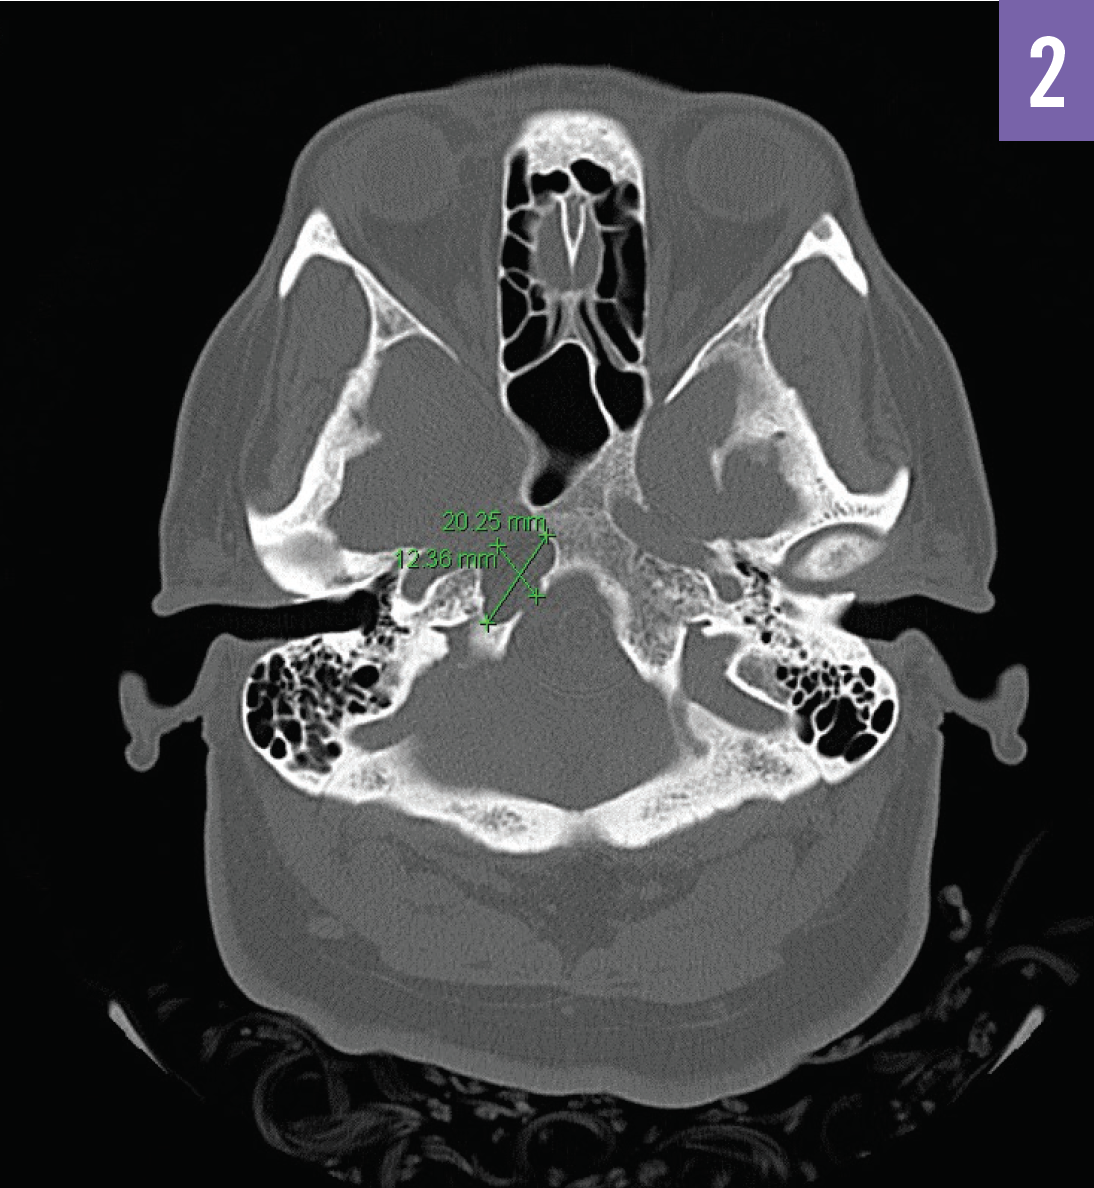

Petrous Apex Mucocele Consultant360

https://s3.amazonaws.com/HMP/c360/imported/Petrous Apex Mucocele Figure 2.png